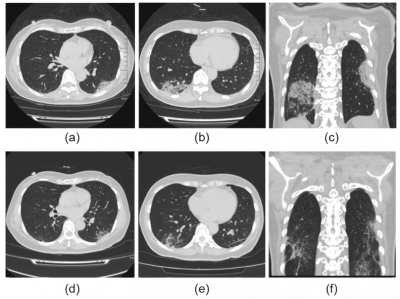

Toplam 80 hasta (deney grubu Favipiravirin verilen 35 hasta ve kontrol grubu da lopinavir/ritonavir verilen 45 hastadan oluşuyor) ile yürütülen çalışmanın sonuçları(16), Favipiravirin, lopinavir/ritonavir’den daha güçlü antiviral etkiye sahip olduğunu gösterdi. Çalışma, Favipiravir ile tedavi edilen hastaların daha hızlı iyileştiğini ve akciğerlerinin kontrol grubundaki hastalardan daha iyi iyileştiğini gösterdi. Favipiravir alan hastaların, tedaviden sonraki dört gün içinde virüs açısından negatif sonuç verdikleri, kontrol grubundaki hastaların ise ancak 11 gün sonra negatif sonuç verdikleri gözlendi. Son olarak da ilacı alanların %91,4’nün akciğerlerinin görüntüleme testlerinde iyi olduğu, kontrol grubununsa ancak %62,2’sinin iyi olduğu gözlendi. Ayrıca Favipiravir alan tedavi grubunda anlamlı bir yan etki görülmezken, lopinavir/ritonavir grubundan da önemli ölçüde daha az yan etkiye sahip olduğu gösterildi.

Favipavir verilmeden önceki göğüs görüntülemesi (a-c). 12 günlük Favipiravir sonrası görüntüleme (d-e).

Kaynak: Q. Cai, M. Yang, D. Liu et al. (2020). Experimental treatment with favipiravir for COVID-19: An open-label control study. Engineering, https://doi.org/10.1016/j.eng.2020.03.007